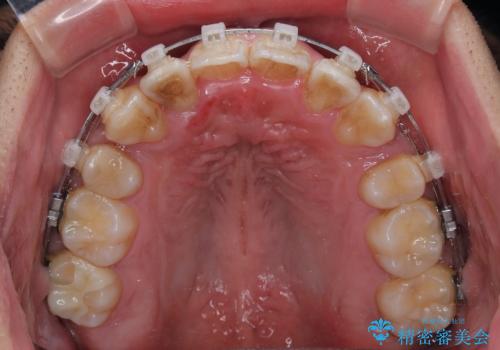

矯正装置は、審美性と費用面のバランスを考慮して、プラスチックブラケットとメタルワイヤーを使用しました。

透明感のあるブラケットを用いたため、従来の金属装置よりも目立ちにくく、日常生活での見た目の不安も軽減できます。